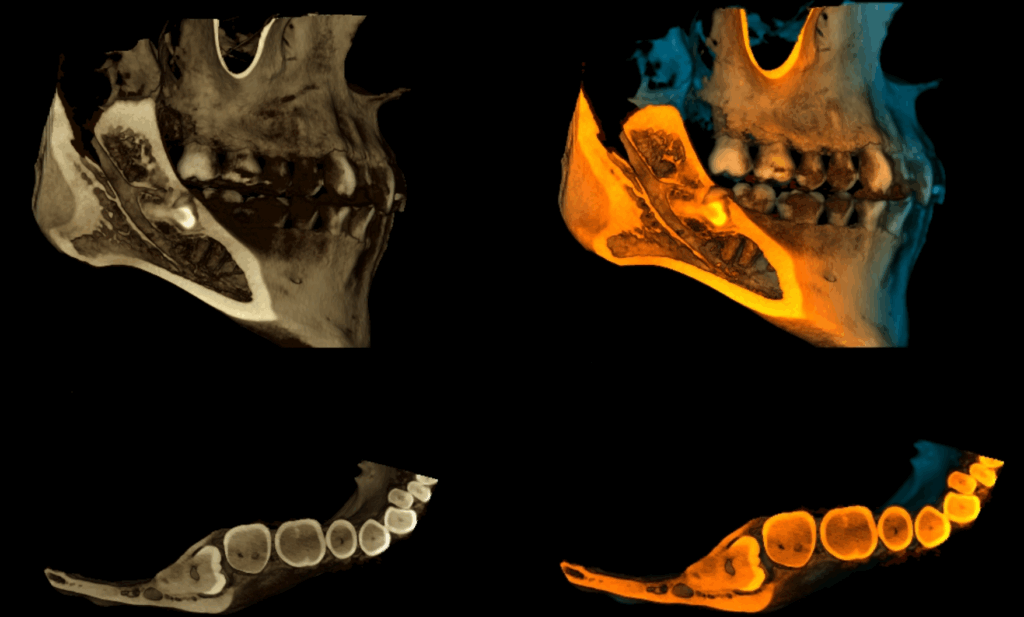

RECONSTRUCCIÓN 3D

caso 344 - RECONSTRUCCION 3D IDM